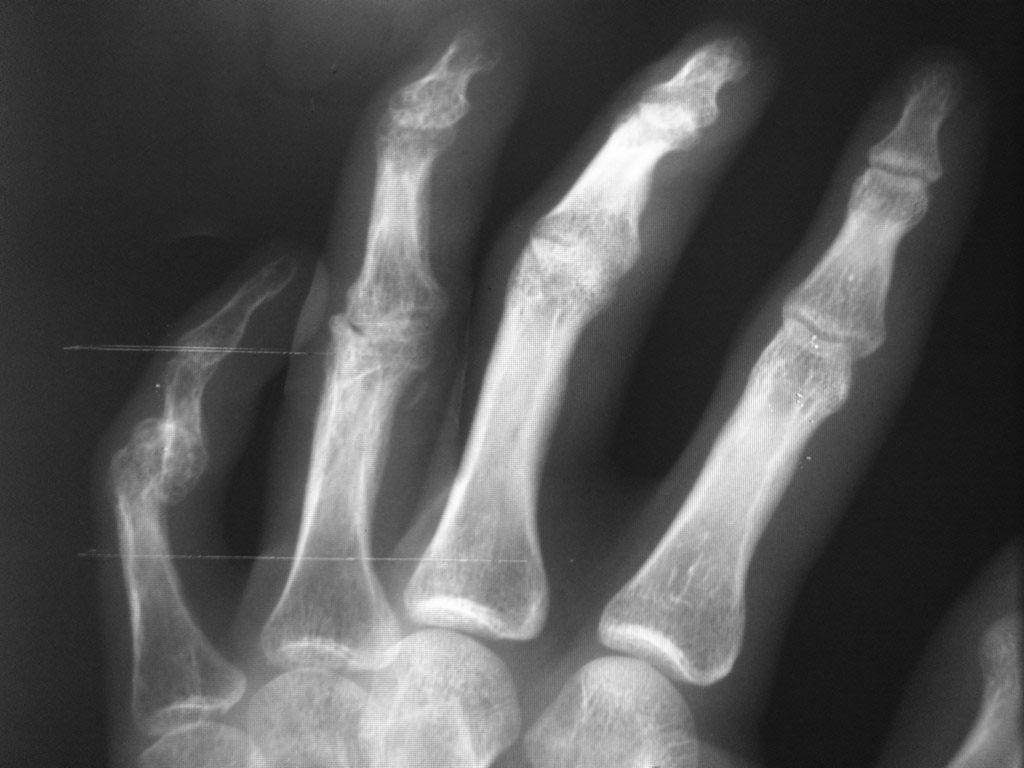

Уважаемые Коллеги! Помогите разобраться с диагнозом, из анамнеза молодой человек 27 лет, порезал руку ножом в области 4 и 5 пальцев правой кисти, в виду особого состояния (запой), только через 2 месяца обратился в одно из травмотделений с резаной раной 4,5 пальцев правой кисти и полным разрывом сухожилий сгибателей, где был произведен неудачно поздний вторичный шов сухожилий сгибателей, после операции стойкая сгибательная контрактура этих пальцев. Далее он обращаеется в другое травм отделение где просит врача выпрямить ему эти пальцы, что врач и сделал (артродез межфаланговых суставов в нефункциональном положении, а полностью разогнутом, прямом). После этого начинается самое интересное - уже ровно год после этих событий непрекращающее гноетечение из свищей 4 пальца на уровне проксимальной-средней фаланги. Ему 4 раза в поликлинике и в одном из хирургических стационаров лечили консервативно и оперировали безуспешно от костного панариция. Когда обратился ко мне на уровне средней фаланги 4 пальца, свищ по ладонной поверхности, типично как при костном панариции (остеомилите фаланги), но когда я посмотрел на снимок костей, то не увидел остеомиелита, небольшой остеопороз, но он не может быть начальным проявлением остеомилита фаланги, так как является временным переходным состоянием секвестрации фаланги и длится не более 2 недель при отсутсвии лечения, а с момента артродеза прошел уже год. Наводит на мысль про хронический гнойный тендовагинит, но разве так долго может длиться процесс суставного панариция, да и неужели только я не вижу остеомилита? Прилагаю фото и рентгенограмму больного. Если тендовагинит, тогда буду проводить или проточно-промывное дренирование или же ваккумное дренирование после ревизии пальца, сам больной так устал, что просил ампутировать палец.

3. ...уже ровно год после этих событий непрекращающее гноетечение из свищей ...- но по рентгенограмму не вижу характерных признаков остеомиелита

Уважаемый Нияз. Если внимательно посмотреть на клинику и рентгенографию пальцев видно, что проекция свища в области несостоятельного артродеза ПМФС IV кисти. Следовательно воспалительный процесс находится в области ПМФС, где не смыкание полости постоянно его поддерживает. Следует выполнить лечение как при остеомиелите свищевой форме.